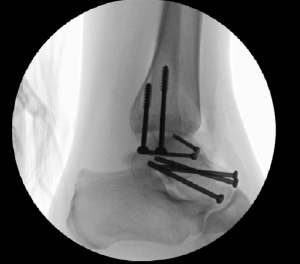

Case 1, Figure 2: 22-year-old female